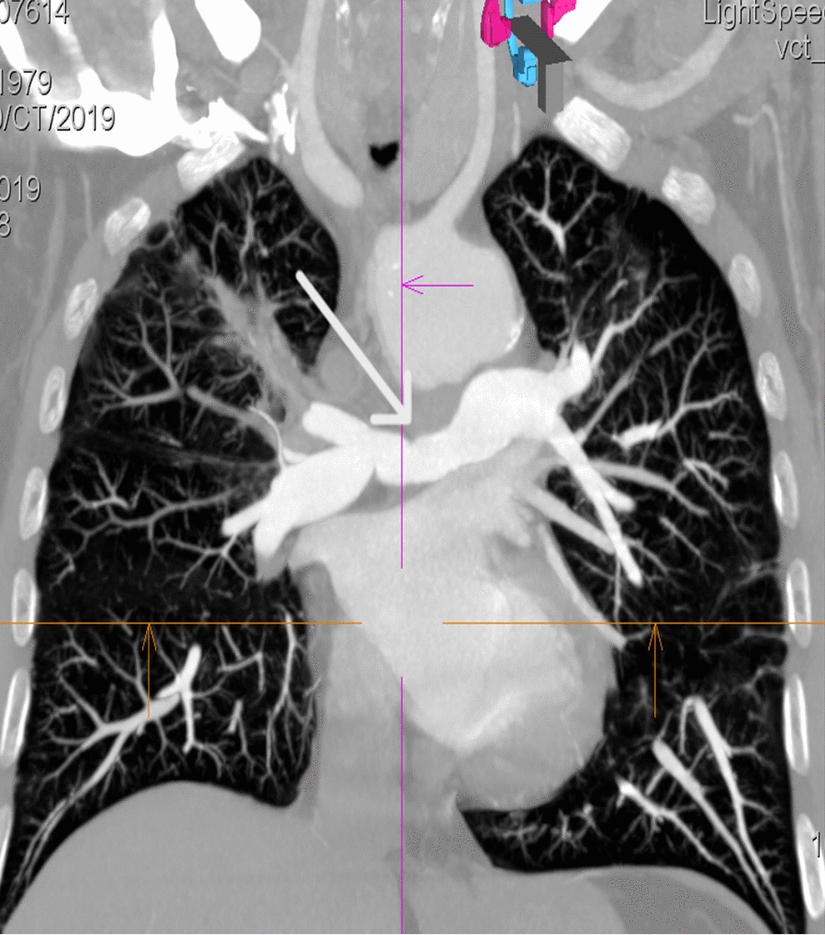

A follow-up angio-CT examination three years after rituximab induction treatment revealed a stable image of the pulmonary arteries compared to the last examination—stenosis of the right pulmonary artery lumen to approximately 10 mm. Due to the nodular lesion in the lung described in the CT scan, which raised oncological concern, an additional PET-CT scan was performed, which showed diffuse, increased metabolism in the wall of the ascending aorta and focally increased metabolism in the course of the right pulmonary artery—the nature of the inflammatory changes. The patient was qualified for another cycle of rituximab treatment. A follow-up chest CT scan after another six months showed stenosis of the right pulmonary artery in the proximal segment to about 6–7 mm over a length of about 40 mm—in retrospective assessment, progression of stenosis (Fig. 2). In the maintenance treatment, methotrexate was reintroduced at a dose of 25 mg/week, due to the improvement in the patient's clinical condition in terms of efficiency, it was not decided to re-administer rituximab.

Fig. 2

On follow-up examination in 2023, progression of narrowing in the right pulmonary artery is showed